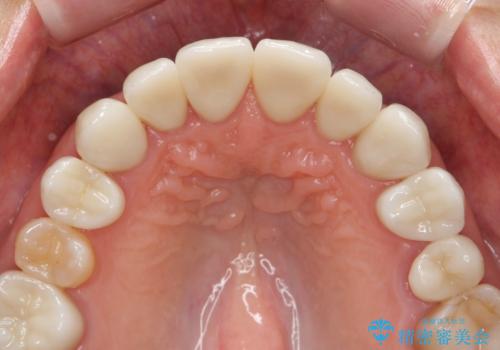

ラミネートよりもより透明感の再現性の高いジルコニアクラウンの出来に喜んでいただくことが出来ました。